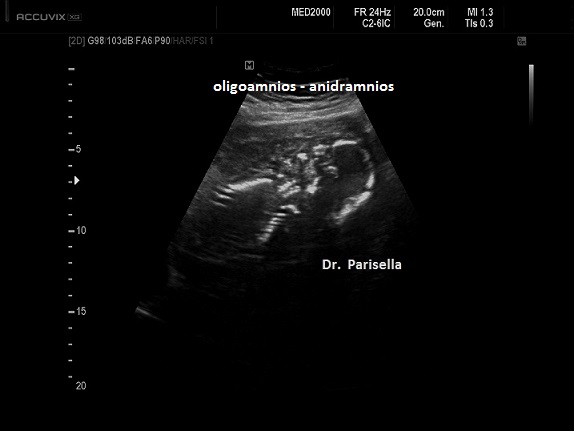

Oligoidramnios

Nell'oligoidramnios la misurazione della tasca massima di liquido amniotico è inferiore a 2 cm. e l'indice di liquido amniotico è inferiore a 5 cm. La tasca singola più profonda è il metodo migliore per la valutazione dell'oligoidramnios e per la valutazione delle gravidanze gemellari. Un liquido amniotico ai limiti inferiori della norma (AFI compreso tra 5 e 8) si può associare a FGR/IUGR (ritardo di crescita intrauterino) o può essere fisiologico a fine gravidanza. Sono essenzialmente tre le cause principali di oligoidramnios prima della 24° settimana (Fetal Medicine Foundation FMF): Anomalie delle vie urinarie, Rottura prematura delle membrane (PROM), Insufficienza uteroplacentare (FGR/IUGR); a queste bisogna aggiungere l'esposizione materna ad alcuni farmaci.